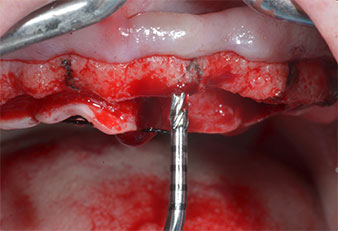

A flame-shaped, diamond-coated piezoelectric instrument (Piezomed I1) was used to mark the implant positions and to perform pilot preparation (Fig. 3). Care was taken to use an up and down movement, with reduced power, full irrigation and low pressure (below 300 g). Next a pilot instrument (Piezomed I2A/I2P) was applied for the initial 2 mm diameter enlargement of the implant sites (Fig. 4), followed by a 3 mm insert (Fig. 5).

Due to the relatively hard bone (D2) in this area, the 10 mm long implant sites at positions 11 and 21 were finalized with a 4 mm diameter rotary drill, in combination with a W&H WS-75 L surgical contra-angle handpiece, the W&H Implantmed implant motor and the optional W&H Osstell ISQ module. In contrast, due to the soft bone the posterior sites were prepared to a final 3 mm diameter using the Piezomed I3P instrument. The implants were finally placed transgingivally to osseointegrate for three months (Figs. 6-10). The existing denture was retained on four provisional implants (Fig. 8).